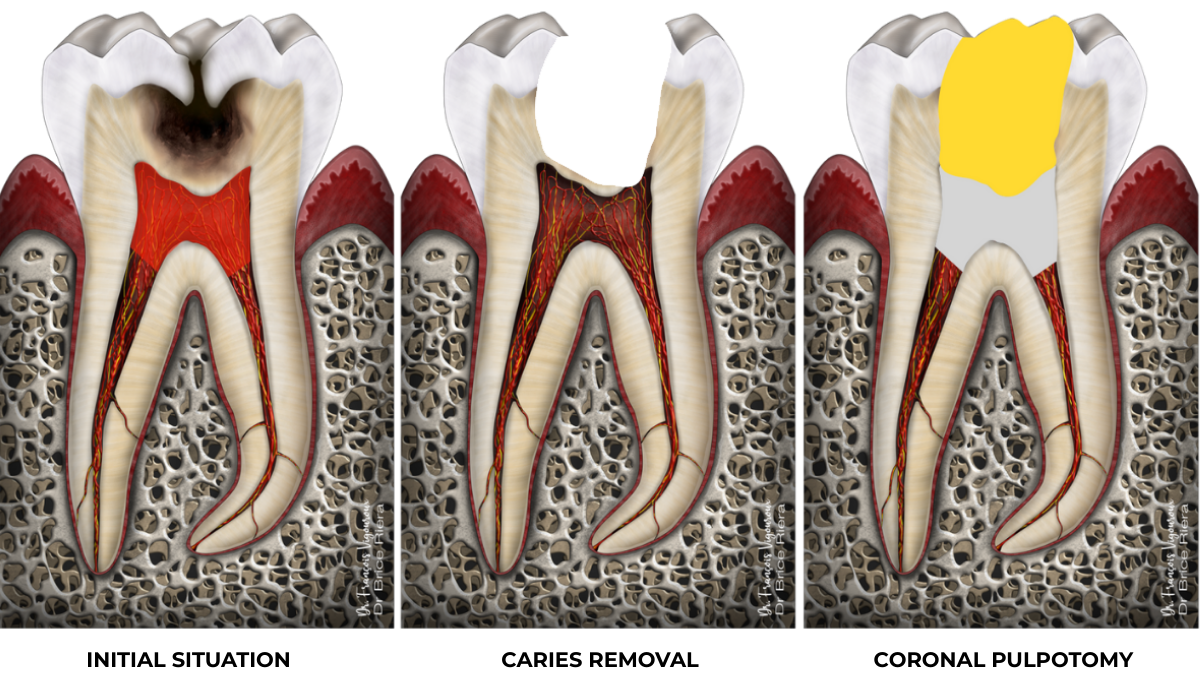

Coronal pulpotomy

Whether during diagnosis or during the procedure itself, it is possible that the coronal pulp cannot be preserved. The coronal pulp is the pulp located in the pulp chamber (left-hand diagram in transparent red).

On the right, in yellow: coronal restorative material / in grey: bioactive biomaterial (such as bioceramic cement)

Clinical case

Full pulpotomy: 91.3% success rate